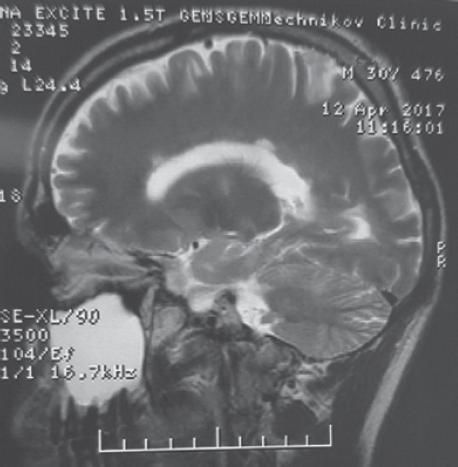

МРТ головного мозга с контрастированием в режимах Т1 и Т2 ВИ. В белом веществе лобных, теменных и левой височной долей с обеих сторон паравентрикулярно и субкортикально, в мозолистом теле, стволе и ножках мозжечка выявляются множественные очаги демиелинизации, имеющие гиперинтенсивный сигнал по Т2, TIRM и изогипоинтенсивный сигнал по Т1.

Без признаков перифокального отека. Общее количество очагов T2/FLAIR — 10–20. В субкортикальных отделах левой лобной доли визуализируется группа кист размером от 0,3 до 0,7 мм в диаметре с минимальной зоной глиоза. Боковые желудочки не расширены, симметричны с умеренно выраженной зоной глиоза по периферии. Умеренная атрофия мозолистого тела. Сразу после введения контрастного вещества выявляется усиление сигнала по типу кольца от единичных очагов в правой лобной доле.

Заключение: «Картина демиелинизирующего поражения головного мозга.

Зона кистозных изменений в субкортикальных отделах левой лобной доли» (рис. 1 и 2).

Рис. 2. МРТ Т1 ВИ больного З. Перивентрикулярная демиелинизация с симптомом «пальцы Доусона», характерным для рассеянного склероза